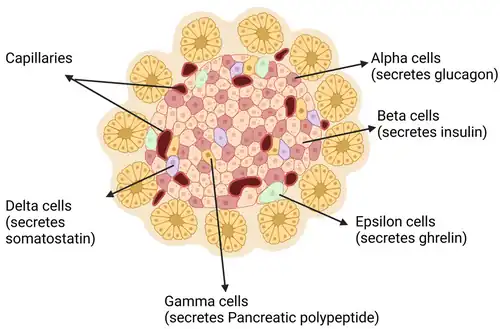

Bètacellen (β-cellen) zijn gespecialiseerde endocriene cellen die zich in de eilandjes van Langerhans van de alvleesklier bevinden en die verantwoordelijk zijn voor de productie en afgifte van insuline en amyline.[1] De vorm van bètacellen zijn afgeknotte piramides die zich clusteren rond de bloedvaten van de eilandjes. Bètacellen hebben een gemiddelde diameter van 10 micrometer (µm).[2] De kern van de bètacel bevindt zich nabij de basis en het insulinegranulaat bevindt zich boven de kern.[3]

Bètacellen vormen ongeveer 50–70% van de cellen in de eilandjes van Langerhans van de mens en spelen een cruciale rol bij het handhaven van de bloedglucosespiegel.[4] Een gemiddeld eilandje van Langerhans bevat in totaal 1000 tot 3000 cellen. Schattingen suggereren dat een muizenalvleesklier 1 × 106 bètacellen (1 mg bètacellen) kan bevatten en een gemiddelde menselijke alvleesklier 1 × 109 bètacellen (1 g bètacellen).[5]

Bètacellen bereiken een nauwkeurige controle van de insulinesecretie door middel van uitgebreide cel-celcommunicatie met de andere celtypen in het eilandje van Langerhans, met name de glucagonproducerende alfacellen en de somatostatineproducerende deltacellen.[26] In bètacellen is de stijging van de bloedglucosespiegel (glycemie) na voedselinname direct gekoppeld aan insulineafgifte. Insulineafgifte is glucoseafhankelijk en wordt, naar analogie van de excitatie-contractiekoppeling in spieren, het stimulus-secretiekoppelingsmechanisme genoemd.